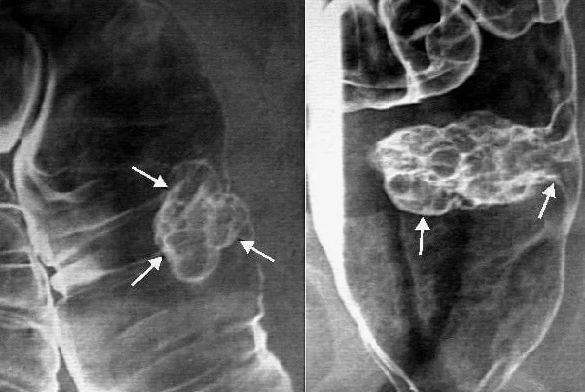

¡En los vasos sanguíneos y el corazón! Precisamente a través de los vasos llega la sangre a todos los órganos internos. Y con la sangre a los órganos internos llegan las sustancias nutritivas y el oxígeno, y también se eliminan las sustancias nocivas – los productos de desecho de las células. ¡Y del corazón depende la presión de la sangre, ¡como de una bomba en el sistema de fontanería!

Cuando somos jóvenes, tanto los vasos como el corazón funcionan de forma estable, por eso todos los órganos internos reciben tantas sustancias nutritivas y oxígeno como necesitan. Sin embargo, con la edad, la cantidad de sangre que llega a los órganos internos, disminuye. Y los órganos internos empiezan a pasar hambre.

Imagínense, por ejemplo, una planta amante de la humedad, a la que un día empezaron a regar menos de lo que necesita. ¿Qué le pasará a esa planta? ¡Sí! Se marchitará y se enfermará. Lo mismo le ocurre a los órganos internos. Y como consecuencia, a toda la salud. Cuando la circulación sanguínea empeora, ellos empiezan a marchitarse y a doler y entonces no realizan las funciones que deberían. Y esto a su vez acarrea otros problemas de salud. ¡Esto crece como una ola!

¿Y por qué empeora la circulación sanguínea? ¡El culpable de esto es el colesterol! Sí, ese mismo del que tanto se habla. Por su estructura, el colesterol se asemeja a la grasa fría. Es decir, es una sustancia muy pegajosa. Con los años el colesterol se acumula en los vasos en forma de depósitos en las paredes internas. Además del propio colesterol, en estos depósitos se involucran otras sustancias, que simplemente se adhieren al colesterol.

Al mismo tiempo, la sangre en el volumen necesario debe llegar a todos los órganos, por eso al corazón no le queda otra opción que aumentar la presión en el sistema. Precisamente por esto es que aparece la hipertensión senil, que, como ya dije, no es una enfermedad, sino que representa una respuesta del organismo a la contaminación de los vasos.